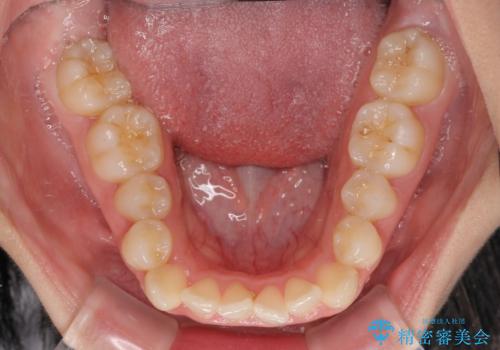

- 上下前歯のデコボコを気にして来院された患者様です。

上顎歯列が下顎の歯列に対して狭小であり、一部下顎の奥歯が上顎よりも外側に位置している状態でした。

上顎の急速拡大装置を使用して上顎骨を側方に拡大することで上顎歯列を拡大し、下顎歯列も拡大できるようにすることで、歯列を整えることとしました。